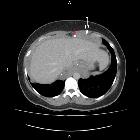

Abdominal and

thoracic lymphangioma with unusual imaging. Diffuse tissue thickening is demonstrated around the liver (white arrow) containing calcification (red arrow).